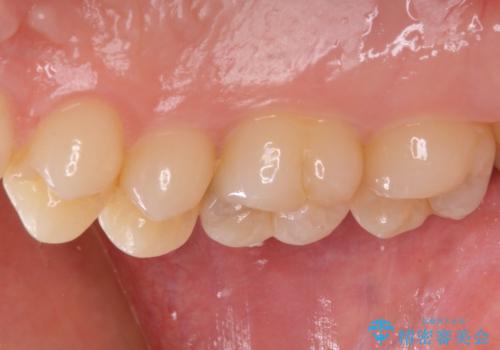

フロスが引っかかる セラミックインレーによるむし歯治療

- ウェブサイトの症例(https://seimitsushinbi.jp/case/9473/)を見て、同じようにフロスが引っかかるとのことで来院された患者様です。

虫歯を除去した後、セラミックインレーにて修復治療を行うこととしました。

セラミックインレー装着後はフロスの引っかかるストレスから解放され、患者様には大変満足していただきました。